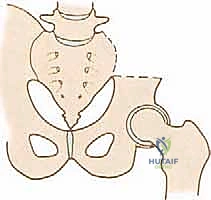

FIG 1 • The bony pelvis and its relation to the major blood vessels, nerves, and visceral organs.